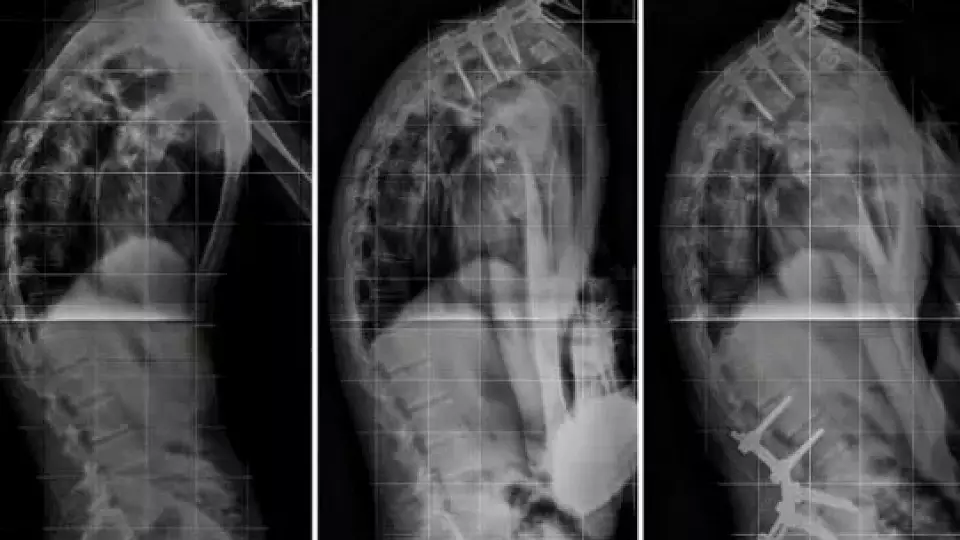

Болезнь Бехтерева заставляет антитела атаковать суставы и хрящи, ведя к их сращиванию и потере подвижности. Но российские ученые разработали первый таргетный препарат, который воздействует на причину заболевания, пишет sovainfo.ru. Первые исследования уже подтвердили его эффективность и безопасность, при этом не «убивая» иммунную систему.